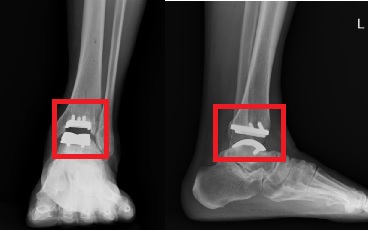

【今傳媒/記者李祖東報導】「我右邊腳踝疼痛腫脹已經很長的一段時間,一開始吃藥還可以改善,但時間一久連吃藥都沒有用了。每次只要一走路就非常痛,痛到讓我每次都只能走幾步而已」,吳女士本身是類風濕性關節炎的病患,身上多處關節或多或少都有疼痛或變形的問題,來到高雄醫學大學附設中和紀念醫院骨科部求診主要是因為右踝疼痛難耐。經X光與理學檢查後,發現病患除了扁平足的問題外,最主要是嚴重的踝關節退化性關節炎;通常嚴重踝關節退化性關節炎的手術治療方式有兩種: 踝關節融合手術及全踝關節置換手術。但因類風濕性關節炎,又同時有扁平足的問題,有日後多個關節退化需關節融合的可能,若此時進行踝關節融合手術,恐怕加速周邊關節的退化,況且病患強烈希望保有踝關節活動度,因此最後為她施行了全踝關節置換手術。術後病人活動良好,半年後就快樂地與家人外出露營旅遊。

這20幾年來,足踝專科醫師嘗試藉由全踝人工關節來保留踝關節活動度,希望可以改善周遭關節提早退化的現象,並增進日常功能的表現。全球的全人工踝關節至少有超過十種不同的設計,目前已進展到第四代。其設計為三件式,為脛骨與距骨金屬組件加上墊片,而目前使用的墊片是超高分子量聚乙烯來降低其耗損。全人工踝關節在超過10年的追蹤,仍有超過8成的良好預後,目前全人工踝關節已躍升成為嚴重踝關節炎病人的另一治療選項。